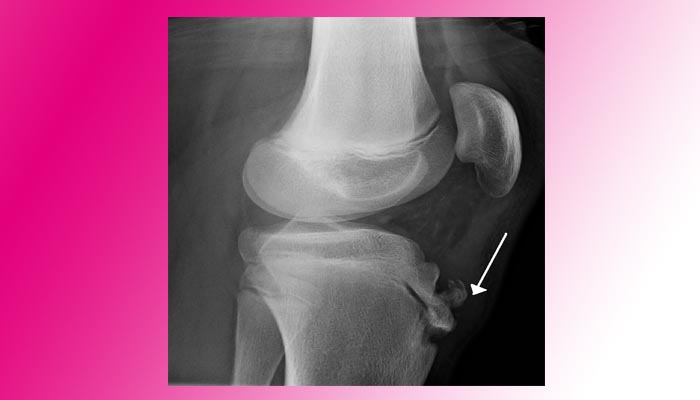

-رادیوگرافی برجسته شدن و گاهی قطعه قطعه شدن برجستگی درشت نی را نشان میدهد .